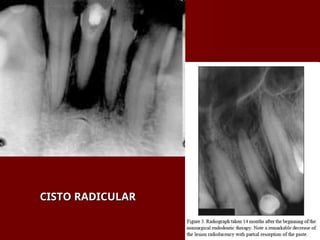

 Cisto Radicular

Cisto Radicular

PATOLOGIA ÓSSEA PATOLOGIA ÓSSEA Osteomielite Osteomielite  Alveolite Alveolite  Osteorradionecrose Osteorradionecrose  Cisto Radicular Cisto Radicular  Cisto Dentíger Cisto Dentíger  Exostose e tórus Exostose e tórus